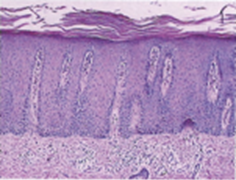

3. 건선피부조직

정상피부

건선피부